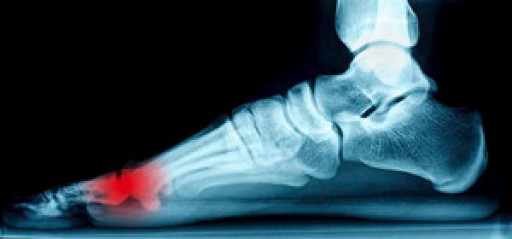

Where Are the Sesamoid Bones Located?

The pain and discomfort that is often experienced with the medical condition sesamoiditis is generally felt under the big toe. Two sesamoid bones are found inside the tendons of the big toe, and can become injured if shoes that are worn do not fit correctly. These types of shoes can include high heels, which typically have inadequate room for the toes to move freely in. A common symptom that many patients experience with this condition can consist of a dull pain that can become stronger as walking and running activities are pursued. It is beneficial to perform exercises that can strengthen the feet, as this may help the foot to generally feel better. If you have pain on the bottom of your foot near the big toe, it is advised that you seek the counsel of a podiatrist who can properly treat this condition.

Sesamoiditis is a condition of the foot that affects the ball of the foot. It is more common in younger people than it is in older people. It can also occur with people who have begun a new exercise program, since their bodies are adjusting to the new physical regimen. Pain may also be caused by the inflammation of tendons surrounding the bones. It is important to seek treatment in its early stages because if you ignore the pain, this condition can lead to more serious problems such as severe irritation and bone fractures.